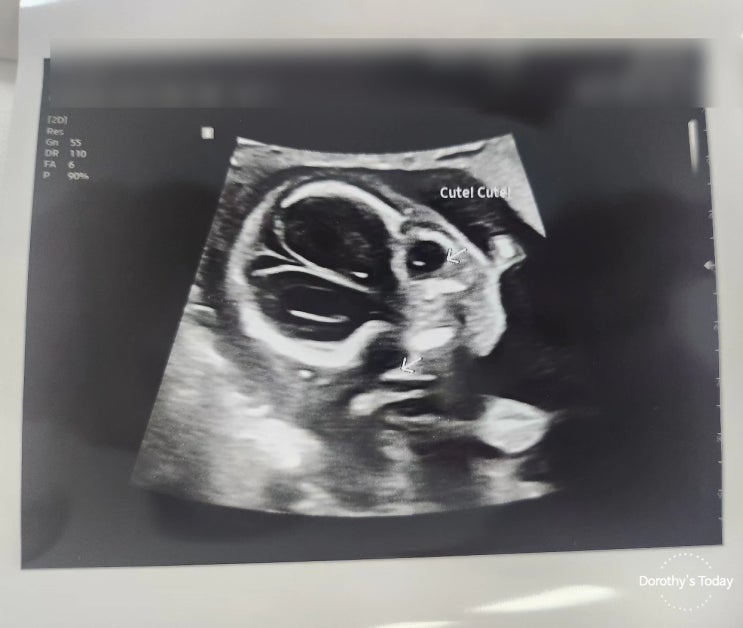

[임신기록] 임신22주차 / 중기 정밀 초음파 검사

2024. 06. 29 (토) 임신 22주차 중기정밀 초음파 동생의 존재를 이해하기 시작하는 우리 첫찌... 멀찍이서 ...